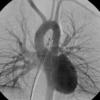

PA angio

Fig 1

Date: 03/23/2004

Views: 3660